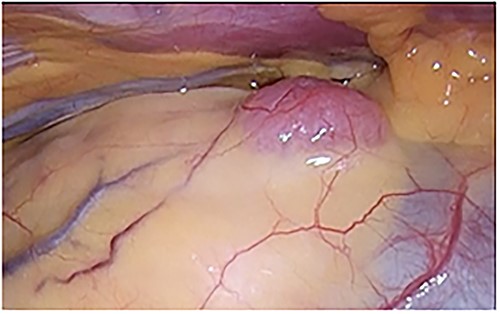

An asymptomatic 42-year-old female, with a history of ulcerative colitis and posterior longitudinal ligament ossification, had a mediastinal tumor detected incidentally on magnetic resonance imaging (MRI) and was admitted to our hospital for surgical intervention. No findings such as ptosis or muscle weakness were observed. Chest non-contrast computed tomography (CT) scans showed a well-circumscribed tumor shadow with a diameter of 18 mm in the anterior mediastinum (Fig. 1). Thoracic MRI revealed a homogeneous tumor with iso-intensity on T1-weighted and low-intensity on T2-weighted imaging. The tumor markers alpha-Fetoprotein, human chorionic gonadotropin, and carcinoembryonic antigen were within normal ranges. Serum anti-acetylcholine receptor antibody levels were normal. The patient underwent partial thoracoscopic thymectomy. The tumor, located at the edge of the right lower pole of the thymus, was smooth, slightly solid, and covered with mediastinal pleura. The pale red color of the tumor was visible from the surface through the pleura, indicating that it was located in superficial layer close to the pleura (Fig. 2). The tumor was resected along with the surrounding thymus with a sufficient resection margin. Gross examination revealed an 18 × 15 mm lobular whitish solid tumor below the pleura (Fig. 3A). Microscopic examination revealed that the tumor was composed of epithelial-like cells with significant lymphocytic infiltration and was divided into several lobules by fibrous septa. However, mitosis was rarely observed (Fig. 3B). The formation of the fibrous capsule was incomplete, and intermittent fibrous tissue was observed around the tumor (Fig. 3C). The surgical margins were negative. The tumor was pathologically diagnosed as a type B1 thymoma [World Health Organization (World Health Organization: WHO) classification], T1aN0M0, Stage I (TNM classification 8th edn), and Stage II, according to Masaoka–Koga staging. The patient was discharged on postoperative Day 7 without any complications. As curative resection was achieved, adjuvant therapy was not planned. Our patient has been followed up for 18 months postoperatively, with no recurrence.

A pale red tumor covered with pleura at the edge of the right lower pole of the thymus.